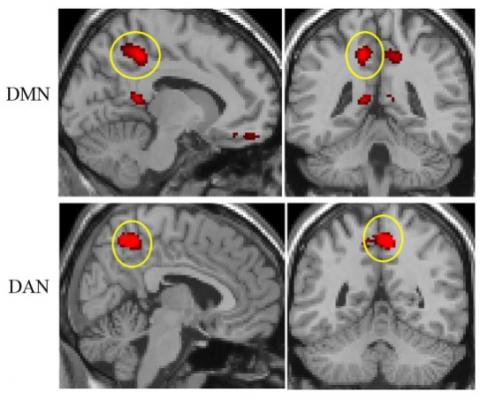

Ainsi, l’acouphène devient identifiable via l’analyse de la connectivité cérébrale : en utilisant l'IRM fonctionnelle (IRMf) pour rechercher des modèles caractéristiques de fonction et/ou de structure du cerveau, la recherche révèle que l'acouphène « prend sa source » dans une zone du cerveau bien précise, le précuneus, situé sur la face interne du lobe pariétal du cortex cérébral. Or le précuneus est relié à 2 réseaux inversement liés au cerveau :

- le réseau d'attention dorsal (dorsal attention network : DAN) qui est actif lorsque le sujet porte son attention sur un objet;

- le réseau du mode par défaut (default mode network : DMN), qui effectue les fonctions « d’arrière-plan » du cerveau lorsque le sujet est au repos et ne pense à rien en particulier.

- Ces 2 réseaux sont inversement liés au cerveau, c’est-à-dire que lorsque le réseau du mode par défaut est activé, le réseau d'attention dorsal est éteint, et vice versa. Or, chez les patients atteints d’acouphènes, le précuneus semble modifier cette relation entre les 2 réseaux : le précuneus est en effet plus fortement connecté au réseau d'attention dorsal et moins connecté au réseau de mode par défaut. Et, plus la sévérité de l'acouphène est élevée, plus ces effets observés sur ces réseaux neurononaux sont augmentés.